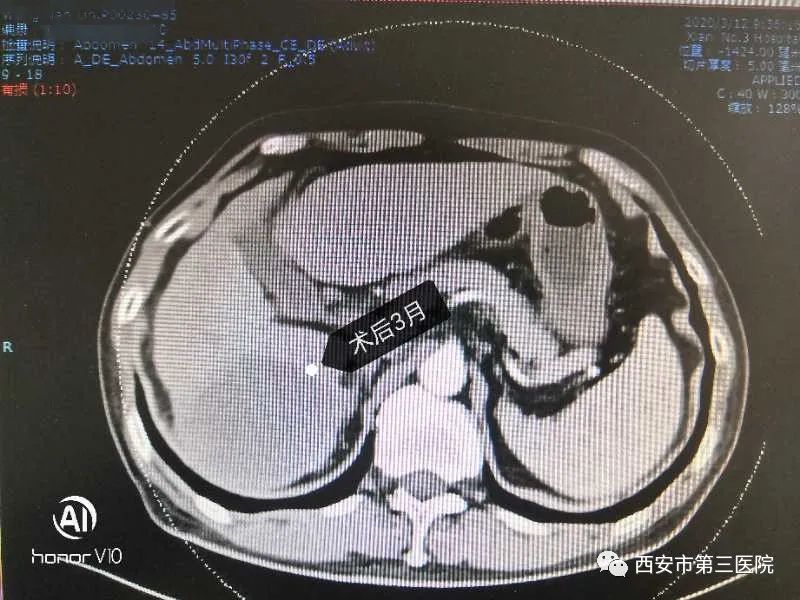

近日,西北大学附属医院•西安市第三医院消化内科为一名肝癌中晚期患者实施D-TACE治疗,术后巨块型肿瘤明显缩小,肿瘤标志物甲胎蛋白从高出正常值数百倍将至基本正常水平;患者原有的腹痛、腹胀症状基本消失,回到正常工作生活。